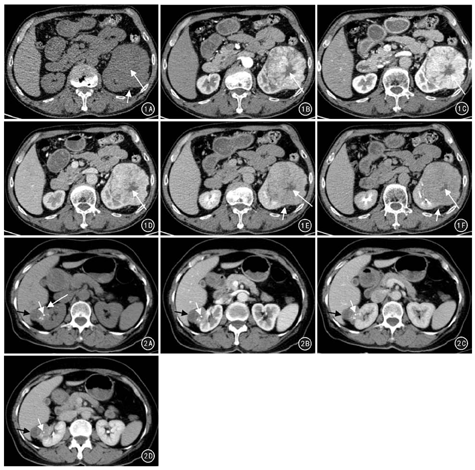

CT检查22例23个病灶(图1、图2)。CT平扫:13个为均匀等密度,10个为略低密度(图1A);23个病灶中可见12个星状瘢痕,3个液性低密度区(图2A),2个点状钙化(图2A)。增强扫描均强化明显,呈"速升缓降"型。皮髓质期病灶实性部分明显强化,其中16个病灶实性部分强化程度低于肾皮质(图2B),7个稍高于肾皮质;实质期8个病灶强化程度近似于肾皮质,15个病灶强化程度低于肾皮质(图1E);12个病灶见"星芒状"瘢痕,呈延迟强化趋势;排泄期21个病灶强化程度低于肾皮质(图1F),2个接近于肾皮质强化。